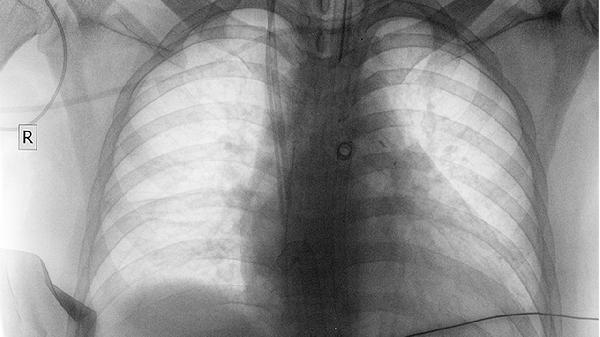

奥希替尼片是第三代EGFR-TKI抑制剂,用于EGFR T790M突变阳性的非小细胞肺癌。相比一代药物能穿透血脑屏障控制脑转移,常见副作用为间质性肺病和QT间期延长。用药期间需定期进行心电图和胸部CT检查。